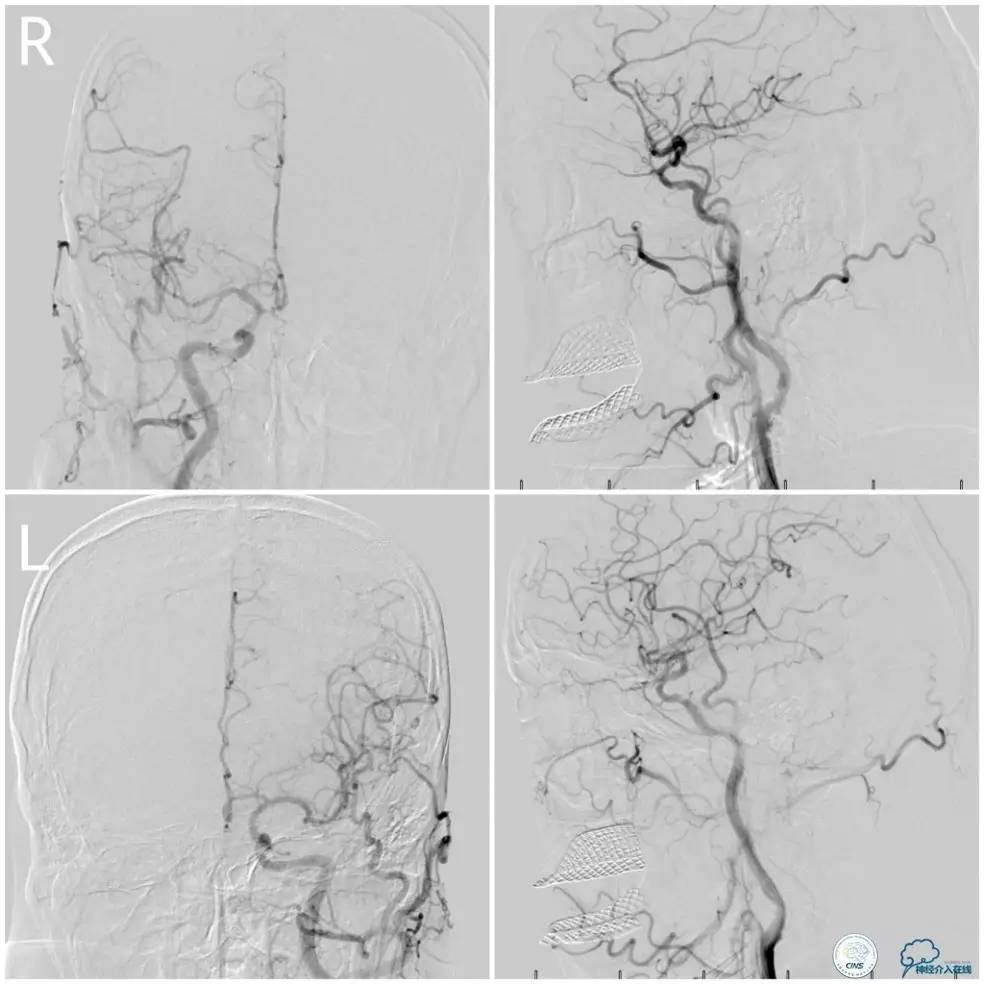

全麻下右侧股动脉穿刺置入8F动脉鞘,6F导引导管到位,送入Traxcess(0.014″200cm)微导丝+Echelon-10微导管谨慎通过右侧椎动脉V1段狭窄处至V2段远端,交换撤出Traxcess微导丝,送入Transend(0.014″300cm)微导丝至V2段远端(图10)。

图10

Ultra-Soft球囊(3.0mm×20mm)于狭窄处预扩张后置入EXCEL支架(4.0 mm× 24mm),球扩后造影见支架贴壁良好,远端血管显影好,前向血流TICI3级。6F导引导管沿微导丝通过右椎动脉V1段支架至V2段(图11)。

图11

此时多体外投照显示右椎V4-基底动脉极重度狭窄,几近闭塞(图12)。

图12

Transend(0.014″300cm)微导丝+Echelon-10微导管,谨慎通过右椎动脉V4段病变后置于右大脑后动脉P1段(图13)。

图13

Gateway球囊(1.5mm×15mm)于狭窄段扩张后放置Wingspan支架(2.5 mm×15mm),撤出微导丝后造影,局部狭窄率50%,支架内中远段见细小充盈缺损,考虑急性血栓形成,予以欣维宁5ml动脉内缓慢注射未见好转(图14)。

图14

遂再次将Transend微导丝送至右大脑后动脉P1段,使用Gateway球囊(2.0mm×15mm)于支架最狭窄处后扩张(图15)。

图15

其后造影显示支架贴壁良好,远端血管显影好,前向血流TICI3级(图16)。

图16

缓慢回撤6F导引导管至锁骨下动脉,造影显示右椎V1段支架无移位,前向血流正常(图17)。

图17